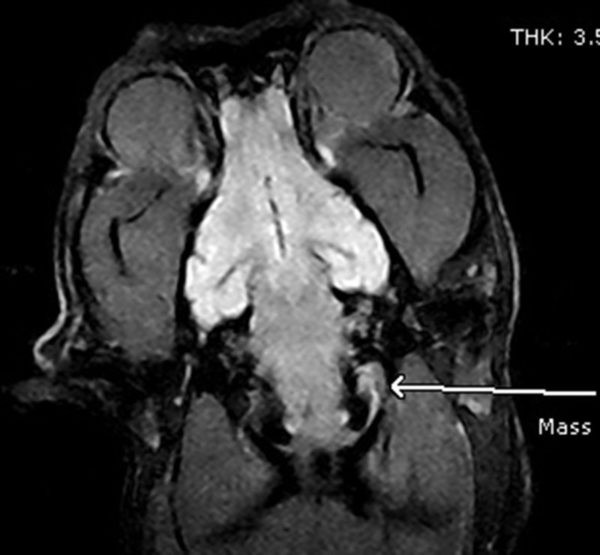

MRI image of a dog's brain.

Dog brain

MRI strength is seen in its ability to image soft tissues structures such as brain, eyes, pituitary gland, spinal cord, nerves, muscles, tendons and can differentiate normal tissue from tumours and various other disease processes.

MRI of the brain is often used to evaluate and define tumour types, infection, seizure disorders, strokes, hydrocephalus and other damage as a result of trauma. MRI of the spine is used for diagnoses of spinal cord tumours or syrinx, herniated disks, spinal cord compression and cord inflammation. Knee and hip MRI can be used to investigate tendon or ligament tears, bone or muscle tumours and inflammation.